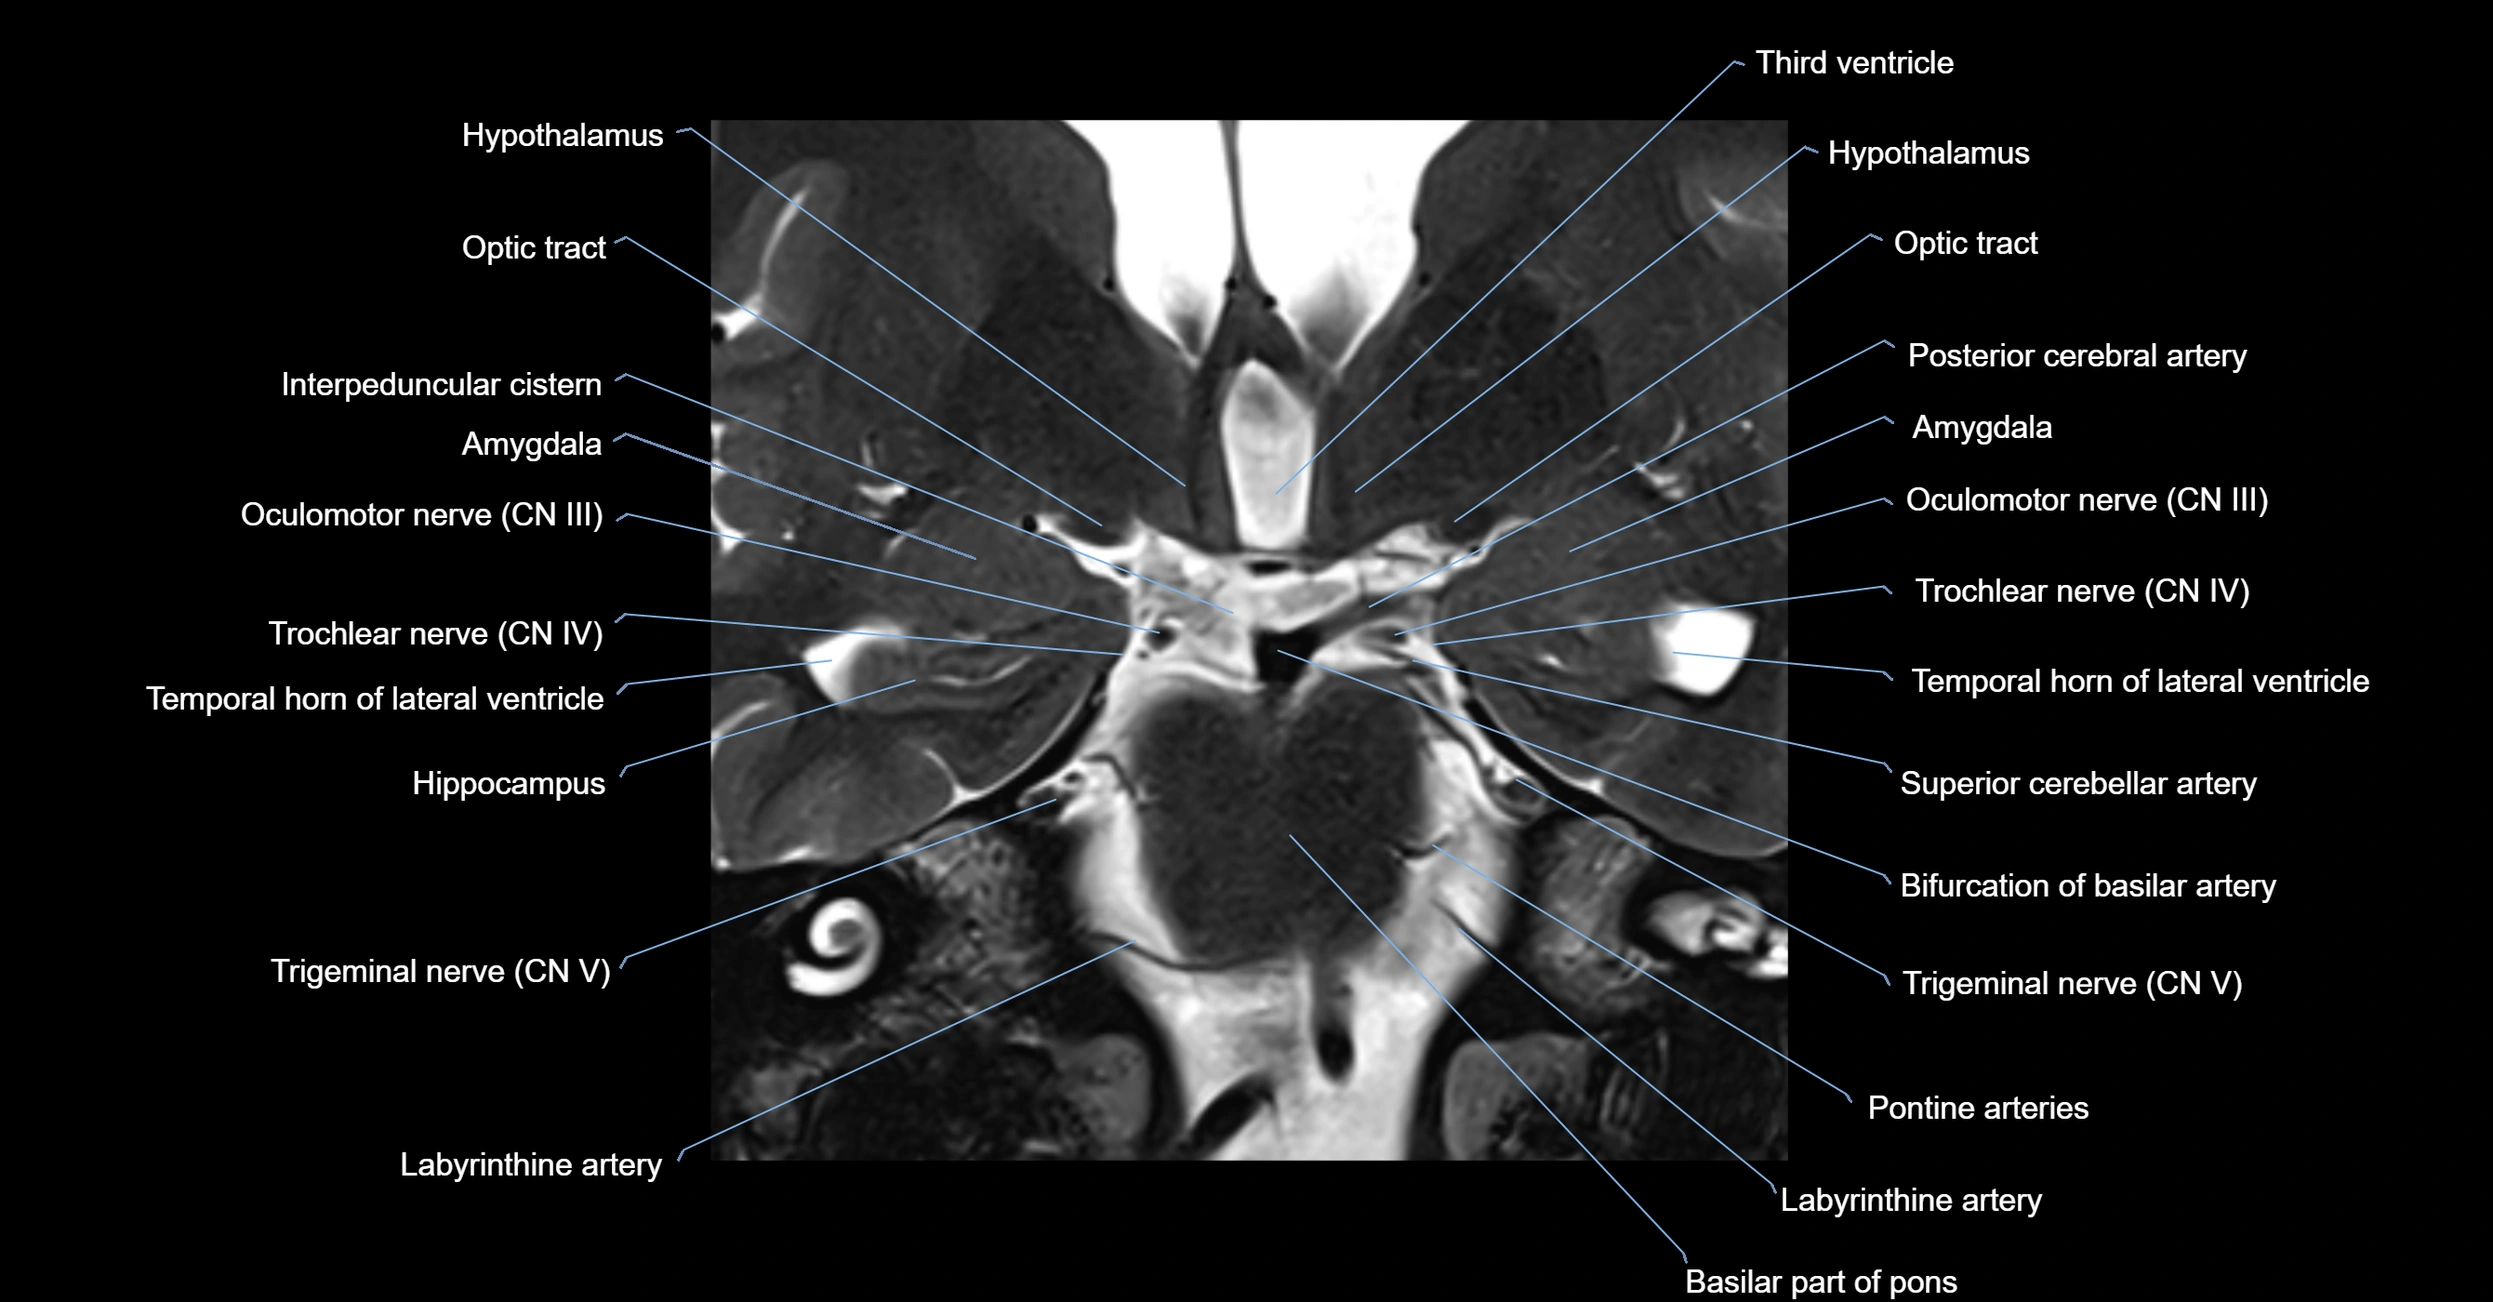

MRI Appearance

-

The abducens nerve is a small, thin, linear structure

Best visualized on high-resolution T2-weighted 3D MRI sequences (e.g., FIESTA or CISS)

Seen as a hypointense (dark) line running from the brainstem at the pontomedullary junction, traversing the prepontine cistern, and entering Dorello’s canal under the petrosphenoidal ligament, then into the cavernous sinus, and finally the orbit

May be challenging to visualize in standard MRI due to its small size

Pathology may be inferred by absence, displacement, or enhancement of the nerve

MRI images